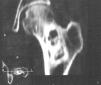

Mujer de 57 años que acude a nuestro hospital por un cuadro de dolor y claudicación en la extremidad inferior izquierda de varios meses de evolución. En la exploración clínica, no había cambios inflamatorios en las partes blandas ni sensación de masa, y las exploraciones neurológica y vascular fueron normales. En la radiografía anteroposterior de cadera izquierda (fig. 1) se visualizaba una lesión lítica en la metáfisis proximal del fémur. No se identificaba ningún tipo de matriz ósea en el interior, y estaba centrada y alineada en el eje longitudinal del hueso. La zona de transición era estrecha y el borde esclerótico, y contenía bandas o septos internos de esclerosis. No se visualizaba reacción perióstica, siendo de apariencia benigna. En este momento se incluyó dentro del diagnóstico diferencial la displasia fibrosa, el quiste óseo simple y el fibroma óseo, sin poder descartar que se tratase de un sarcoma de bajo grado.

Fig. 1.--Radiografía simple de fémur izquierdo. Lesión lítica metafisaria, sin matriz ósea interna y de borde esclerótico.